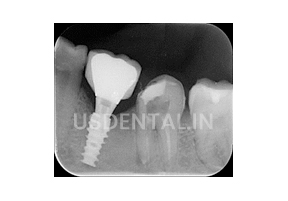

After 3 months we placed an implant and here is the x-ray after the procedure.

In x-ray, we have found that the lesion of infection has cured to a great extent and the patient was getting improvement also.